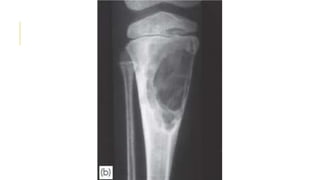

GIANT-CELL TUMOR

Giant-cell tumour is a lesion of uncertain origin that appears

after the end of bone growth.

Most commonly in the distal femur, proximal tibia, proximal

humerus and distal radius.

About one-third of these tumors remain truly benign; one-third

become locally invasive and one third metastasize.

Present as pain at the end of a long bone; sometimes there is

slight swelling.

Pathological fracture occurs in 10–15% of cases.

x-ray show a ‘cystic’ (i.e. radiolucent) area situated eccentrically

at the end of a long bone. Unlike any of the other ‘cystic’ lesions,

it always extends right up to the subchondral bone plate.

Treatment : well defined lesion with benign histology could be

treated by curettage and bone grafting While aggressive lesions

GIANT-CELL TUMOR Giant-cell tumouris a lesion of uncertain origin that appears after the end of bone growth. Most commonly in the distal femur, proximal tibia, proximal humerus and distal radius. About one-third of these tumors remain truly benign; one-third become locally invasive and one third metastasize. Present as pain at the end of a long bone; sometimes there is slight swelling. Pathological fracture occurs in 10–15% of cases. x-ray show a ‘cystic’ (i.e. radiolucent) area situated eccentrically at the end of a long bone. Unlike any of the other ‘cystic’ lesions, it always extends right up to the subchondral bone plate. Treatment : well defined lesion with benign histology could be treated by curettage and bone grafting While aggressive lesions